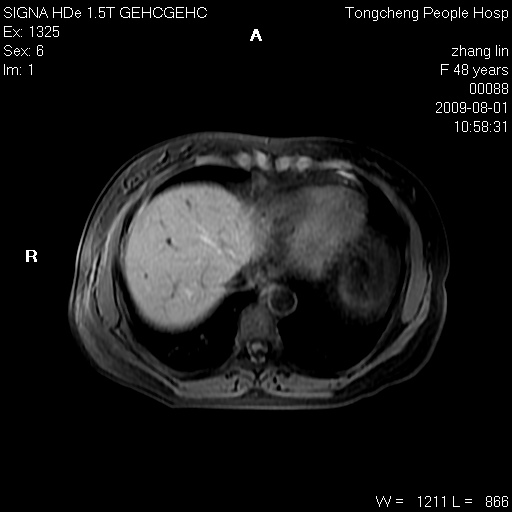

女,48岁。健康体检,彩超发现右肾占位性病变。平素健康。

临床诊断:右肾占位性病变,性质待定(囊肿?肿瘤?)。

上中腹部mr平扫+增强扫描,图像如下:

右肾上极见一类圆形病灶,t1wi呈等信号t2wi呈等高混杂信号,三期增强无强化,边界清---考虑囊肿出血。